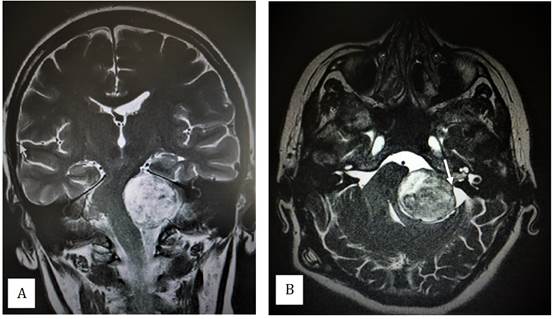

La resonancia nuclear magnética (RNM) de cráneo reveló una tumoración a nivel del ángulo pontocerebeloso izquierdo de 32x26 mm compatible con un shwannoma vestibular, con compresión y desplazamiento del IV ventrículo, bulbo y protuberancia del mismo lado, causando dilatación secundaria del sistema ventricular supratentorial (Figura 1).

Figura 1: Resonancia Magnética cerebral luego de derivación ventrículo peritoneal. A. Corte coronal en T2 mostrando tumoración hiperintensa a nivel del ángulo pontocerebeloso izquierdo que determina compresión y desplazamiento de tronco encefálico. B. Corte axial en FIESTA (secuencia de elección para valorar relación tumoral con pares craneanos). Se observa tumoración hiperintensa heterogénea compatible con schwannoma vestibular con imagen característica del componente canalicular ocupando el conducto auditivo interno ipsilateral (flecha). Ejerce gran efecto de masa comprimiendo y desplazando el tronco encefálico.